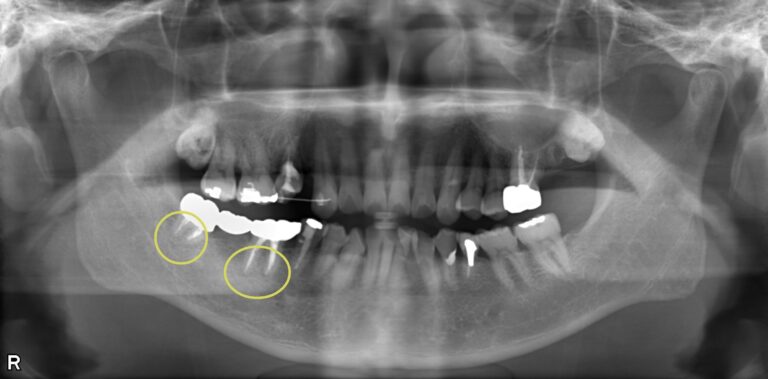

| 歯科用CTによる三次元診断 | 拡大ルーペの使用 |

| 一般的なレントゲン(二次元)では見えない、歯根の複雑な構造や病巣の位置を立体的に正確に把握し、治療の見落としを防ぎます。 | 肉眼では困難な根管内の細部を約8倍に拡大して確認し、処置の精度を高めます。 |

| 歯科用CTによる三次元診断 |

| 一般的なレントゲン(二次元)では見えない、歯根の複雑な構造や病巣の位置を立体的に正確に把握し、治療の見落としを防ぎます。 |